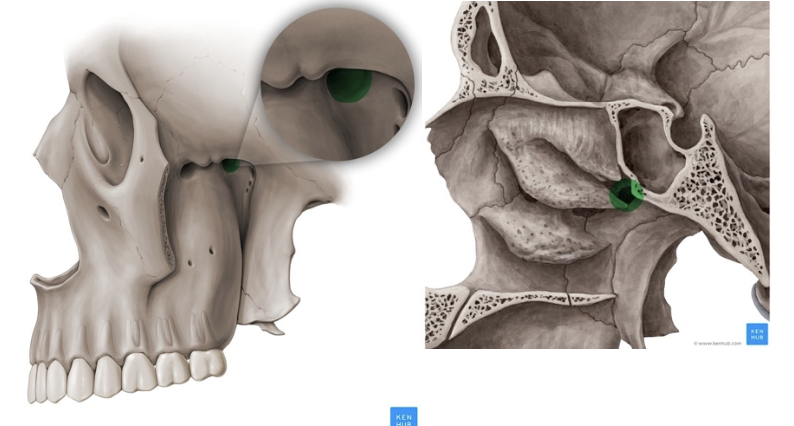

Hueso palatino

(es cara interna porque se ven las crestas)

(parte interna = fosas nasales

parte externa = maxilar superior)

LO MAS ATRAS EN LAS FOSAS NASALES

Escotadura esfenopalatina

Forma el agujero esfenopalatino en la hendidura esfeno maxilo palatina

Apófisis orbitaria del palatino

forma parte del piso de la órbita

Tiene las SEMI CELDAS que se unen con el etmoides para formar senos etmoidopalatinos

Apófisis esfenoidal del palatino

Apófisis piramidal del palatino

Articula con la tuberosidad del maxilar anteriormente

Lámina vertical del palatino

Lámina horizontal del palatino

Agujero esfenopalatino

Uno de los 8 agujeros de la hendidura pterigomaxilopalatina